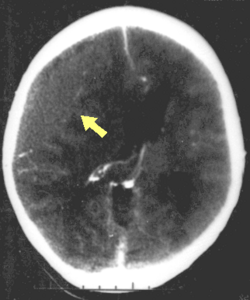

CT scan showing spread of the subdural hematoma (single arrows), midline shift (double arrows)

Systems also exist to classify TBI by its pathological features.[20] Lesions can be extra-axial, (occurring within the skull but outside of the brain) or intra-axial (occurring within the brain tissue).[24] Damage from TBI can be focal or diffuse, confined to specific areas or distributed in a more general manner, respectively.[25] However, it is common for both types of injury to exist in a given case.[25]